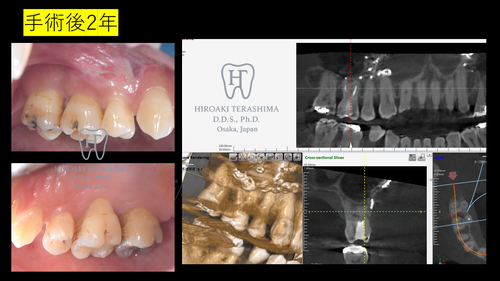

- 術後2年:歯肉退縮はあるものの、ポケットは4㎜以下、出血なし

- Ⅲ度分岐部病変は保存困難とされるが、適切な診断・精密手術・再生材料の選択により良好な結果が得られた